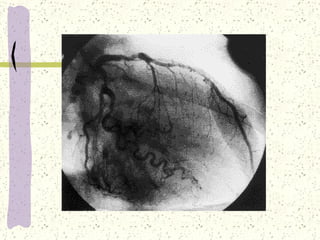

VENTRICULOGRAFIA

Circulación Coronaria: El miocardio recibe sangre procedente de las arterias coronarias izquierda y derecha. Estas parten de la aorta justo por encima de la válvula aórtica. El flujo disminuye durante la sístole pero aumenta después durante la diástole. El flujo de sangre que circula por el miocardio, depende de las demandas miocárdicas de oxígeno.

... En reposo el corazón extrae del 60 a 70% del oxígeno presente en la circulación coronaria. Cuando las demandas de oxígeno exceden la capacidad de la circulación coronaria se produce la isquemia miocárdica. El corazón es drenado por las  venas cardiacas. Las venas que drenan el ventrículo izquierdo vierten en el interior del seno coronario y después entran en la AD. Varias venas que drenan sangre del VD vierten en el interior de la AD y VD.

Arteria Coronaria derecha: Abastece a la AD, el VD. El aspecto posterior del septo (90%). El músculo posterior y papilar. Los senos y nódulo AV(80 a 90%) Aspecto inferior del VI. Arteria circunfleja: Abastece a la AI. Las superficies posteriores del VI. El aspecto posterior del septo.

Arteria coronaria izquierda: ( Descendente anterior izquierda) ADA Abastece la pared ventricular izquierda anterior. El septo interventricular anterior. Las ramas septales del sistema de conducción, el haz de His y las ramas. El músculo papilar anterior. El ápex ventricular izquierdo.